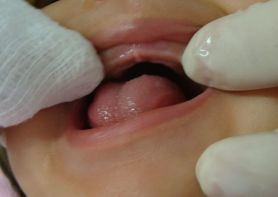

Dentición y patologías bucales en el bebé

La salida de los dientes de tu bebé es una gran etapa. En algunas ocasiones puede venir acompañada con algunos malestares o fiebre. Conoce los consejos de pediatras y odontopediatras para manejar la salida de sus primeros dientes de la mejor manera.

La dentición en bebés y sus síntomas aparecen en promedio entre los 8 y 12 meses de edad, cuando aparece el primer diente.